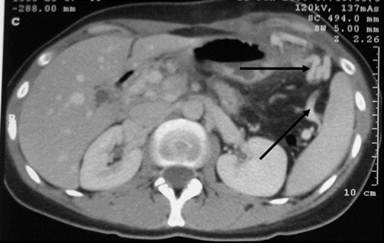

The nasogastric tube was removed on the third postoperative day. Oral intake started 5 days after surgery. The hospital stay was 12 days. Pathologic findings showed a well-differentiated neuroendocrine tumor. No postoperative diabetes mellitus or exocrine insufficiency was noticed. The patient continues to be well after a 10-month follow-up without pancreatic insufficiency or local recurrence, and CT has demonstrated real splenic perfusion by the collateral vessels on CT (Figures 5 and 6).

Figure 6. Perfusion of collateral splenic veins on contrast- enhanced CT. |